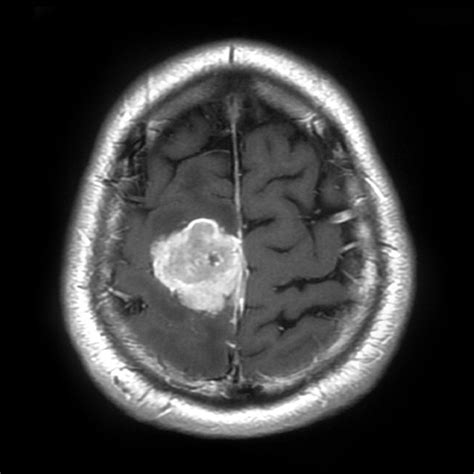

• Imaging Tests: Imaging tests such as X-rays, CT scans, MRI scans, and PET scans can help visualize the tumor or tumour and determine its size, location, and extent.

• Biopsy: A biopsy involves removing a small sample of tissue from the tumor or tumour for examination under a microscope. This can help determine whether the tumor or tumour is benign or malignant.